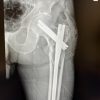

Computed tomography scan confirmed the continuity. Soft-tissue density lesion noted in the medial aspect of Hoffa’s fat pad and knee joint with multiple loose bodies in anterior and lateral aspects of patella-tibial joint and tibiofemoral joint (Fig. 3). Synovial chondromatosis/osteochondroma may be considered. Diagnosis was based on clinical and imaging findings: An osteochondroma of the posterior aspect of patella was confirmed. Given the patient’s significant symptoms and the impact on her daily activities, surgical excision was deemed necessary. Surgical procedure: A medial parapatellar approach was used to access the lesion [6,7]. Excision: The osteochondroma was excised en bloc, ensuring complete removal of the cartilaginous cap. Intraoperative findings were consistent with pre-operative imaging. The wound was irrigated and closed in layers. Hemostasis was achieved, and the extensor mechanism was carefully preserved (Fig. 4).

Figure 4: Intraoperative images.